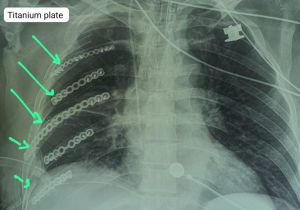

सड़क दुर्घटना में बुजुर्ग की पसली हो गई थी चकनाचूर, टाइटेनियम प्लेट की नयी पसली बनाकर बचाई जान

15 Sep, 2023 12:51 PM IST | SAMIKSHASAGAR.COMरायपुर आठ दिन पहले 63 वर्षीय बुजुर्ग जो राजिम के रहने वाले हैं एवं पेशे से...